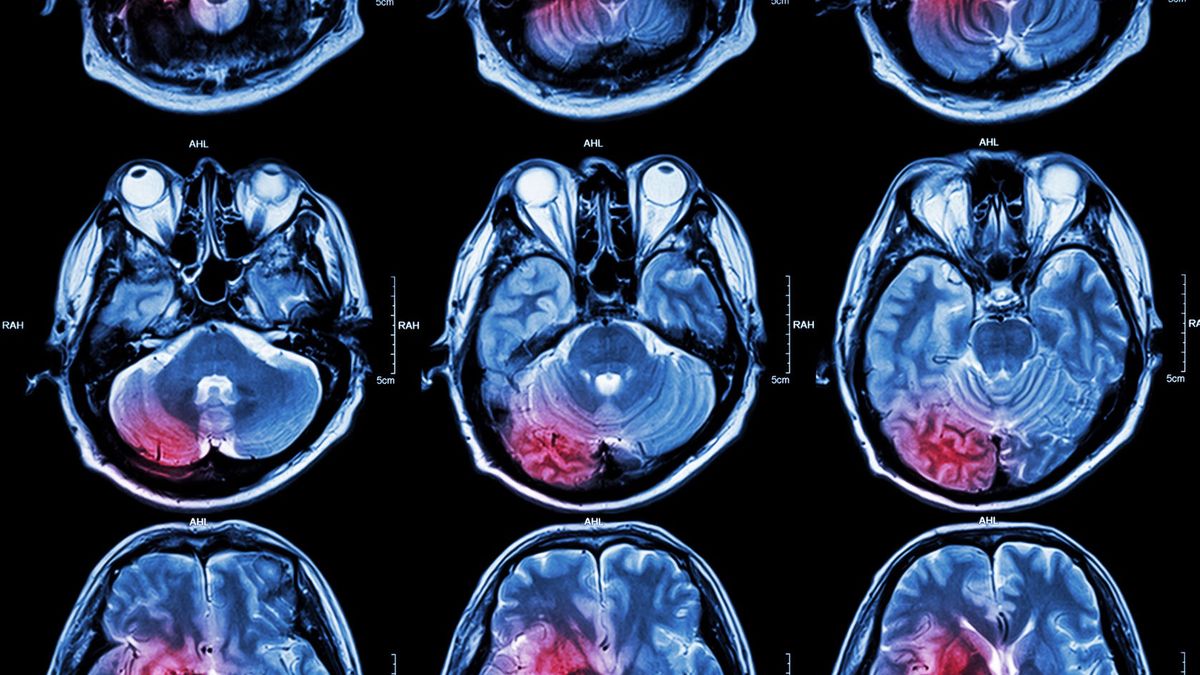

Naukowcy z Uniwersytetu Australii Zachodniej w Crawley przeprowadzili badania pod kątem wpływu warzyw kapustnych na funkcjonowanie naszego układu krwionośnego. Ich wyniki opublikowano na łamach "Journal of the American Heart Association". Eksperci postanowili sprawdzić zależność między regularnym spożywanie, kalafiora, brukselki i brokułów a kondycją zdrowotną tętnicy szyjnej. Grubość ścianek tego naczynia tętniczego wpływa na stopień ryzyka wystąpienia poważnych chorób, takich jak zawał serca i udar mózgu. W badaniach wzięło udział 945 kobiet po 70. roku życia.

Uczestniczki eksperymentu naukowego poddały się badaniom ultrasonograficznym i wypełniły kwestionariusze, w których odpowiadały na pytania dotyczące swojego codziennego sposobu odżywiania. Australijscy naukowcy mieli na celu zbadanie obecności blaszek miażdżycowych w tętnicy szyjnej. Jak się okazało kobiety sięgające codziennie po warzywa kapustne miały mniej zanieczyszczone tętnice szyjne. Wnętrze naczyń tętniczych kobiet z dietą bogatą w tego rodzaju produkty było szersze o około 0,5 mm.

Ta pozornie niewielka różnica w grubości ścianek tętnic obniża ryzyko udaru mózgu nawet o 20 proc. W profilaktyce udaru najskuteczniejsze okazało się jedzenie brokułów, brukselki i kalafiora.